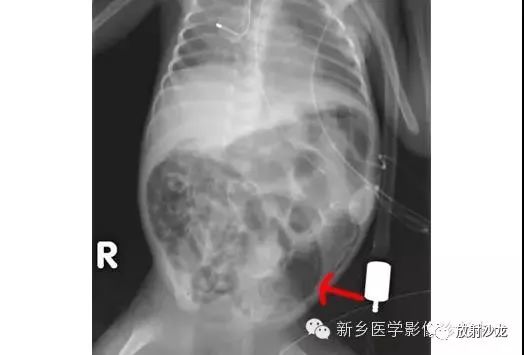

上图符合53岁,女性,肠梗阻所做的腹部平片。发病初所拍图像在左侧,24小时后所拍图像在右侧。是什么原因造成病人梗阻?众多发现都在眼前,不要被箭头影响。

该患者存在一个大的盲肠肠扭转。左侧图像显示一个没有任何可见结肠袋(短箭头),内脏充满大量气体。在升结肠(红色箭头)存在粪便与空气,这表明没有完全阻塞并且一些气体正向远端移动。右图像显示内脏位置的变化,这表明梗阻是非固定的。扭转是由弯曲的箭头所圈出。典型的表现为盲肠头朝向右侧髂窝与肠扭转突出向上朝向左上腹部。